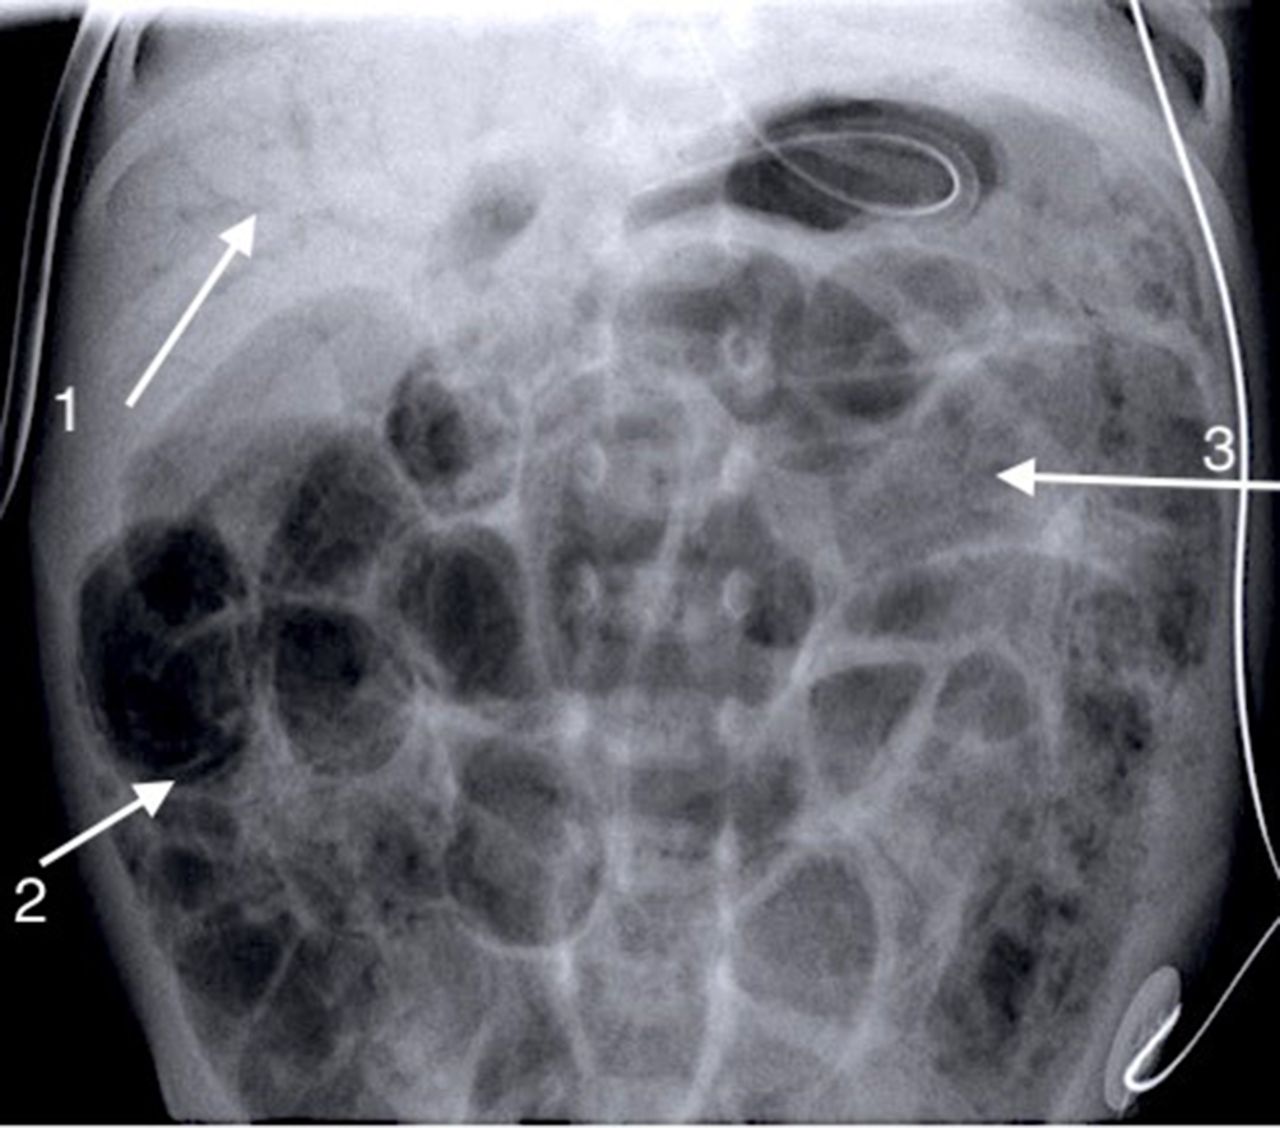

How to use abdominal X-rays in preterm infants suspected of developing …

Paralytic Ileus – Totally Rad Patho